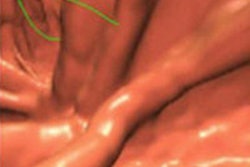

![]() |

| Electronic cleansing artifacts caused false positives resulting from untagged feces, pseudoenhancement of tagged materials (above), and air-contrast-wall interface (below). |